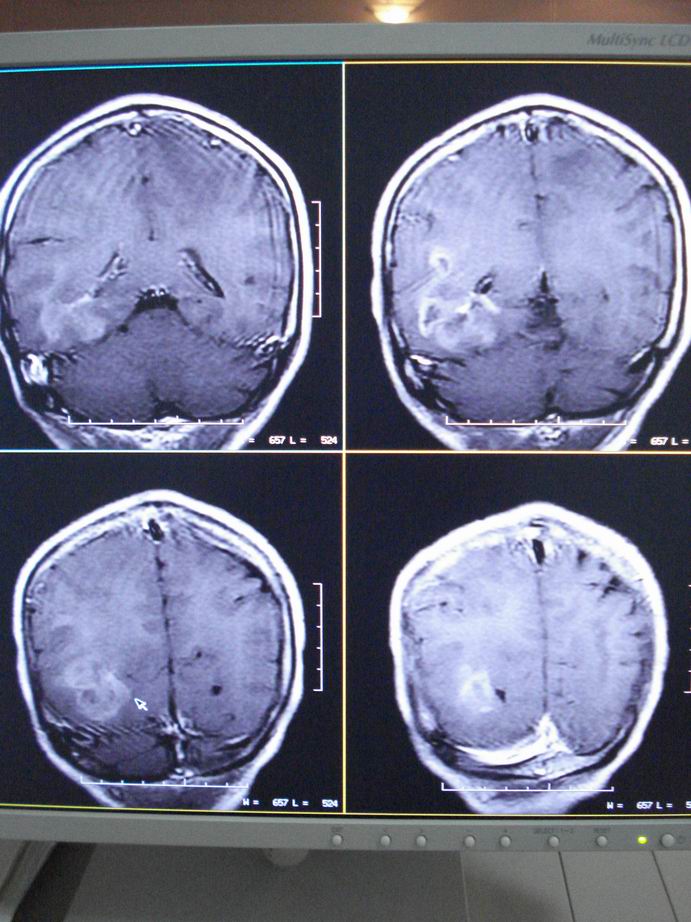

男60岁,左侧肢体乏力及精神异常10天,血压正常,血常规,肝肾功正常,腰穿无异常,请教颅内多发病灶,考虑什么?感染?肿瘤(转移性?)还是其它?

考虑为颅内多发转移瘤

脑内多发性转移瘤。

淋巴瘤较转移瘤可能大。

脑内多发占位性病变,首先考虑感染性病变,其次是转移瘤。

结合病人高龄,考虑转移瘤